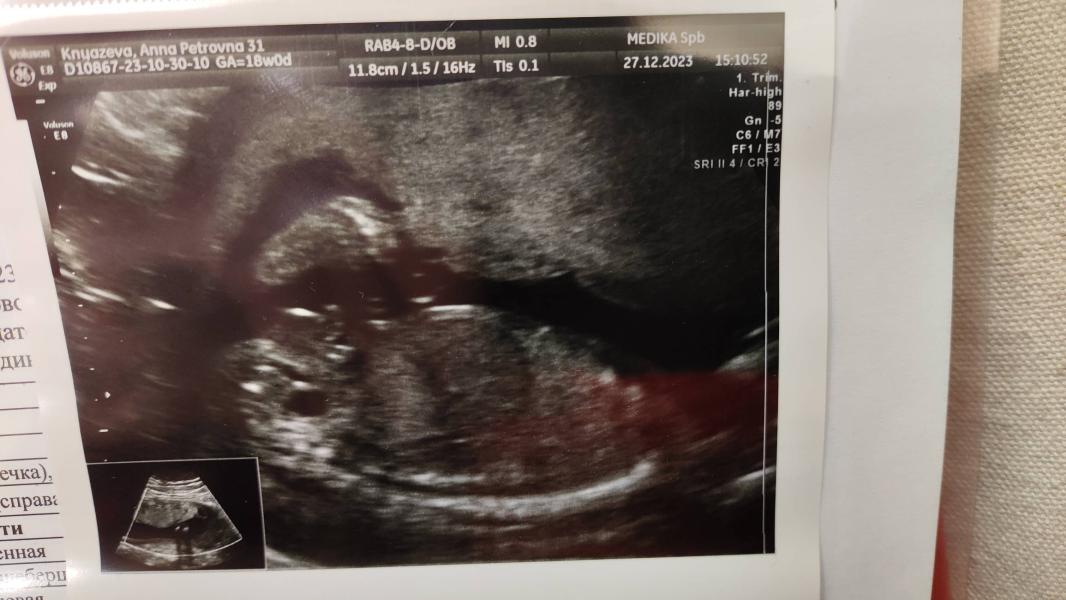

Сделала УЗИ, сказали будет мальчик: переживаю, перепутали или нет, срок 17,6, нет перегородки

post image 1

Сделала узи, сказали мальчик 🚙

Надеюсь это точно, не перепутали и ничего не отвалится к следующему узи😂

Немного смущает, что не нашли полость прозрачной перегородки, по узи сейчас 17,6, надеюсь просто чуть позже, что это нормально